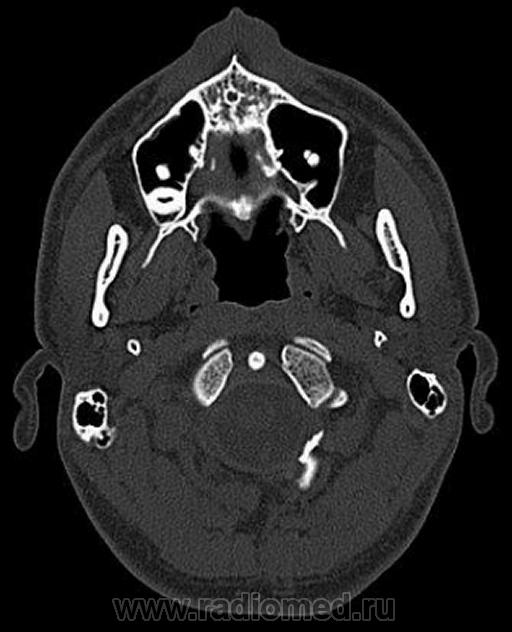

Два случая....

1. Эктопия зуба?

2. Хронический гайморит?